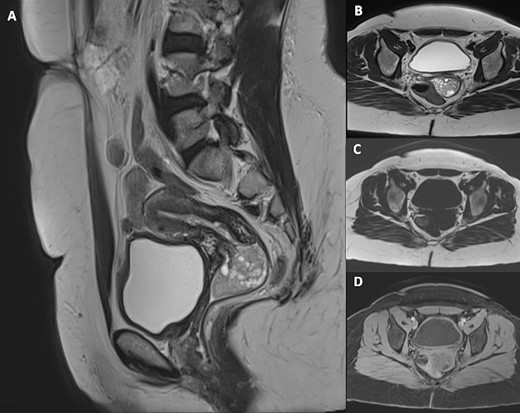

Pelvic magnetic resonance imaging (MRI) revealed a 5 cm × 3 cm × 3 cm intravaginal mass, with endocervical implantation, well-defined, featuring slightly lobulated margins and an oval shape. The mass exhibited the same signal as the endometrium: isointense on T1-weighted images, moderate hypersignal T2 intensity, containing areas of marked hyperintensity on T2. There was no diffusion restriction, and a slight enhancement was observed after Gadolinium injection (Figs 2 and 3). This finding primarily suggested a cervical polyp delivered through the uterine cervix.

Pelvic MRI including sagittal T2-weighted (A), axial T2-weighted (B), axial T1-weighted (C) and axial post-Gadolinium injection (D) images, demonstrating a 5 cm × 3 cm × 3 cm intravaginal mass with endocervical implantation. The mass is well defined, featuring a slightly lobulated oval shape. It exhibits the same signal as the endometrium: isointense on T1-weighted images, moderate hypersignal T2 intensity, containing areas of marked hyperintensity on T2 with slight enhancement after Gadolinium injection.

Pelvic MRI on Diffusion sequence and ADC mapping reveals no diffusion restriction, indicated by an elevated ADC value of (1.5 × 10)–3 mm2/s, suggesting benignity.

Nonetheless, when dealing with cervical polyps, conventional imaging techniques may encounter limitations due to the lesion’s challenging location. In these instances, pelvic MRI is particularly advantageous [5]. The standard MRI protocol include sagittal, oblique axial and oblique coronal views with T1 and T2 weighting, as well as diffusion and contrast sequences. Notably, Diffusion imaging is integral for distinguishing between endometrial cancer, polyps, hyperplasia and normal thickening of the endometrium [11].

Indeed, on MRI, cervical polyps are typically visualized as multicystic lesions on sagittal T2-weighted images, filling the endometrial canal or issuing from the cervix, exhibiting varied signal intensities on T1 and T2 sequences and contrast enhancement [11]. They are isointense relative to the myometrium in diffusion-weighted imaging, a feature confirmed by elevated apparent diffusion coefficient (ADC) values, aiding in their characterization [12].